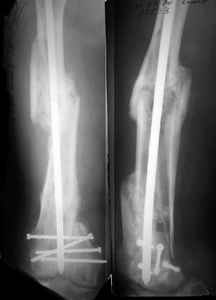

I presented a series of ~25 such cases at EuroTrauma'2004. Many cases were discussed here. I attach am example. Look also recent cases at http://www.hwbf.org/hwb/conf/alex58/scfx.htm,

http://www.hwbf.org/hwb/conf/alex63/alex63.htm

I do realize that you are master surgeon, and congratulations on another excellent, spectacular case (result), but,

- Your last posted case: how is possible to have secure fixation with applied construct without additional casting, bracing or Ilizarov?

THX, initial images are

1,

2.

At that moment we had in stock only the 10 mm solid nails so of course there was no idea about early weight bearing. But it was quite enough for early knee ROM excersises (see attached). Two locking screws through the distal block provided that.